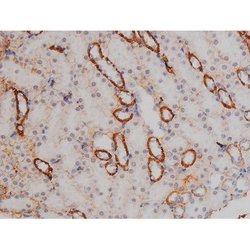

Invitrogen™ Phospho-NPM1 (Thr199) Polyclonal Antibody

Antibody detects endogenous levels of Nucleophosmin only when phosphorylated at Threonine 199.

| Applications | Immunohistochemistry (Paraffin), Western Blot, Immunocytochemistry |